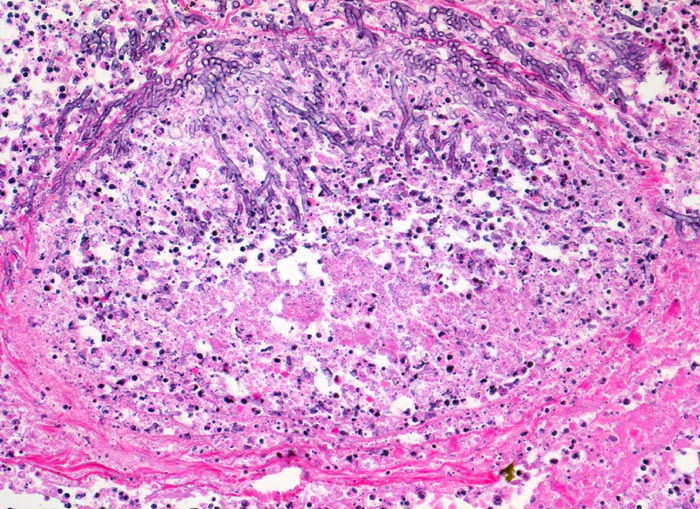

Morphologische Merkmale:

• Multiple Herde mit zentraler Nekrose und hämorrhagischem Randsaum.

• Pilzmyzelien, zerfallende neutrophile Granulozyten und Erythrozyten im Zentrum der Herde.

• Kräftig gefärbte Pilzhyphen mit 45° Verzweigungen.

• Hämorrhagischer Randsaum um die Nekrose: Hyperämische Alveolarwandkapillaren. Alveolen angefüllt mit Blut, Fibrin und Alveolarmakrophagen.